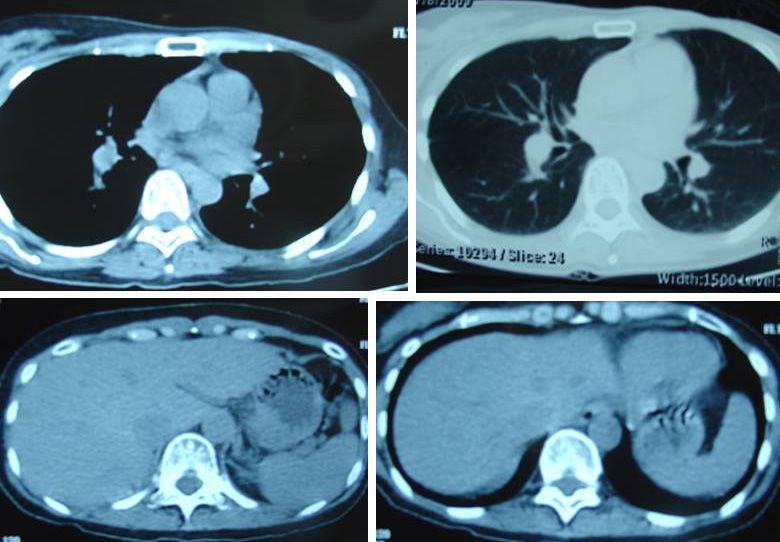

Fay (not real name) is 44-years-old. In July 2015, she found a lump in her left breast.

- Mammogram showed a cluster of subtle heterogenous microcalcifications in the left breast, suspicious of malignancy.

- Ultrasound confirmed the presence of a 1.5 x1.0 x 1.3 cm irregular lobulated hypechoic mass lesion at 2 o’clock of left breast.

- A fine needle biopsy confirmed a ductal carcionoma.

Fay proceeded to have a mastectomy in September 2015. Histopathology of the left breast and axillary lymph nodes indicated:

- Invasive micropapillary carcinoma, grade 3 with in situ carcinoma.

- Lymphatic and vascular invasion by malignant cells seen with metastasis to 3 of 12 lymph nodes.

- Nipple and excised surgical margins are free of neoplasia.

- Receptor status: Tumour cells are positive for ER, PR and c-erb-B2.